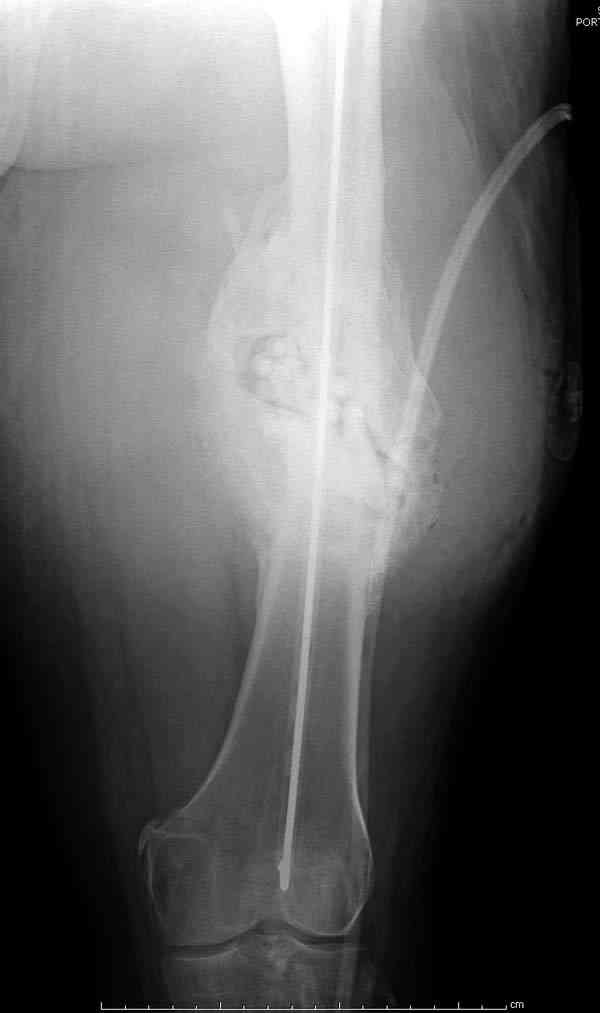

Через 3 года после травмы констатировало отсутствие консолидации бедренной кости, сохранение признаков хронического остеомиелита (свищ в нижней трети левого бедра). Произведен демонтаж аппарата, реостеосинтез бедренной кости спице-стержневым аппаратом, некрсеквестрэктомия. В аппарате удалось лишь частично произвестиустранение углообразной деформации бедренной кости [image 05] .

Через 4,5 лет после травмы выявлены рентгенологические признаки консолидации перелома, признаки хронического остеомиелита купировались. Аппарат был демонтирован. Пациент продолжил ходьбу с дозированной нагрузкой на конечность при помощи костылей. Через 2 месяца начал ходить при помощи трости. Однако, еще через 2 месяца отметил появление свищей на бедре с гнойным отделяемым и укорочение длины конечности. При осмотре в январе 2007 г.: пациент ходит при помощи костылей без опоры на левую нижнюю конечность, на бедре имеются множественные рубцы, на наружной поверхности сегмента в верхней и нижней третях имеются два свищевых хода со скудным серозно-гнойным отделяемым; отечности тканей конечности нет, пальпация безболезненная, отмечается укорочение длины конечности на 5 см, патологическая подвижность не определяется, имеется стойкая разгибательная контрактура коленного сустава (разгибание - 180 гр, сгибание - 170 гр), признаков нарушения кровоснабжения и иннервации тканей конечности нет. Температура тела нормальная. В общих анализах крови и мочи отклонений от нормы нет. [image 06,07, 08 (стрелками отмечены свищевые раны, 09, 10]Дорогие коллеги, я уверен, что у многих из вас после знакомства с данным клиническим наблюдением появится множество вопросов, касающихся уже проведенного лечения (особенно, сроков и способов). Сразу оговорюсь - я не смогу правильно ответить на многие вопросы (особенно касающиеся предшествующего периода лечения). Прошу вас, конечно по возможности, сосредоточить внимание не на разборе допущенных ошибок (проведенного лечения), а помочь добрым советом относительно тактики наших дальнейших действий. Наверное, кто-то располагает бесценным опытом лечения подобной патологии.